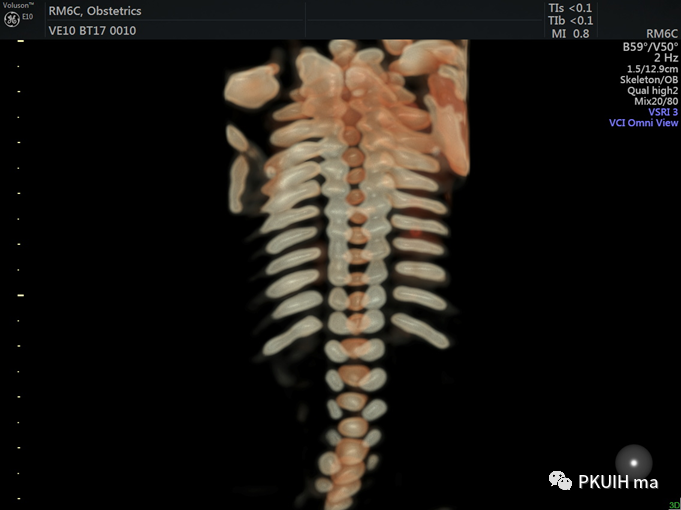

骨骼模式显示整个肋骨,还可以采用水晶成像,更加直观美观

一键快速定位脊髓圆锥位置